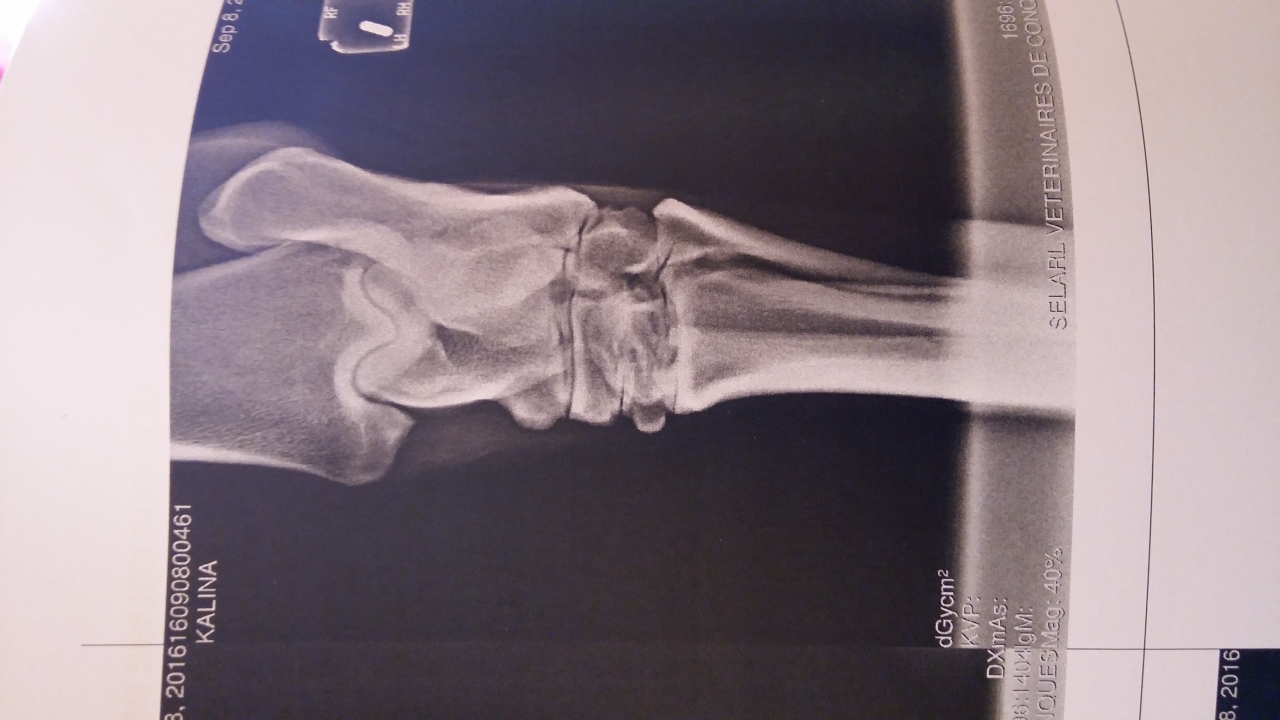

| Dire merci | Bonjour à tous ! J'ai amené ma jument de 18 ans à la clinique Lenormand pour des douleurs significatives sur l'antérieur droit et une tare molle sur le jarret gauche. pour la parenthèse cette tare molle est apparue en janvier suite à un mauvais coup. A l'époque le veto n'avait pas voulu faire de ponction et avait diagnostiqué un épanchement de synovie. Il n'y avait aucune douleur mais il y a quelques semaines j'ai noté douleur + augmentation de la taille de la tare Radios antérieurs Le veto s'est concentré sur les pieds uniquement parce que pour lui gros problème d'appui très visible à l'examen préliminaire. Je rappelle que ma jument est pieds nus. AG ![]() AD ![]() Radios postérieur gauche ![]() ![]() ![]() Bilan du véto Jument présentée pour une enflure en partie externe du jarret gauche. La distension implique la gaine tarsienne pas d'anomalie locomotrice, flexion négative. Boiterie AD sur cercle à main droite. La jument présente un aplomb AG avec des talons fuyants et un pied AD très légèrement encastelé. On note une diminution de l'appui sur l'AD. Radiographiquement on note une faible épaisseur de sole à G et à D. Présence de lésion d'éparvin marqué au niveau intarsien distal et tarso metarsien ainsi qu'une prolifération osseuse importante au niveau du sustentaculum tali. Echographiquement la prolifération osseuse vient en contact du tendon fléchisseur profond sans image de lésion du tendon visible. En conclusion distension de la gaine tarsienne G avec prolifération osseuse sur le sustentaculum tali à l'origine d'une tendinopathie chronique. Douleur aux pieds avec faible épaisseur de sole. Il est préférable de ferrer les antérieurs si la jument continue à avoir une activité. La gaine tarsienne a été infiltrée avec de la triacinolone. L'effet est probablement temporaire la distension devrait revenir plus ou moins rapidement en fonction de l'activité de la jument. Une intervention chirurgicale sous AG est possible [...] mais aujourd'hui elle ne présente aucune boiterie. |